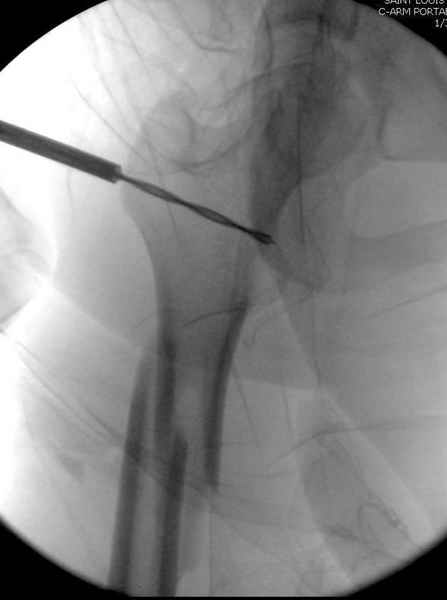

Как раз недавно у меня был примерный случай: больному 36 лет, поступил ночью, травма в результате мотоциклетной аварии, кроме чрезвертельного и спирального перелома левого бедра имеется переломы костей предплечья с этой же стороны. Скелетное вытяжение, а на следующий день больной про оперирован на ортопедическом столе с дистракцией. Чтобы не расколоть чрезвертельный перелом провели временную спицу ближе к переднему кортексу, из малого разреза костодержатель для репозиции, а фиксацию провели антиградным штифтом. Этапы операции на снимках.

DK> Чтобы не расколоть чрезвертельный перелом провели временную спицу

DK> ближе к переднему кортексу,

Второй случай тоже репозиция из малого доступа, больному 19 лет, множественные огнестрельные повреждениия конечностей, живота и черепа, правая конечность холодная, без пульсации. Ортопедический диагноз: огнестрельный перелом правого бедра. При срочной ангиографии повреждения сосудов не подтвердилось, конечность из-за ургентности состояния больного зафиксирована временным наружным фиксатором и больной оставлен на операционном столе для срочной лапаротомии хирургической службой.

Больной долго оставался нестабильным, только на 14 день удалось заменить на антеградный интромедуллярный штифт TFN (trochanteric femoral nail) SmithNephew. После неудачной попытки закрытой репозиции, несмотря на использование "joystick", проксимальный стержень от

наружного фиксатора, (перелом начал срастаться) репозицию провели из малого доступа, затем остальные этапы операции.